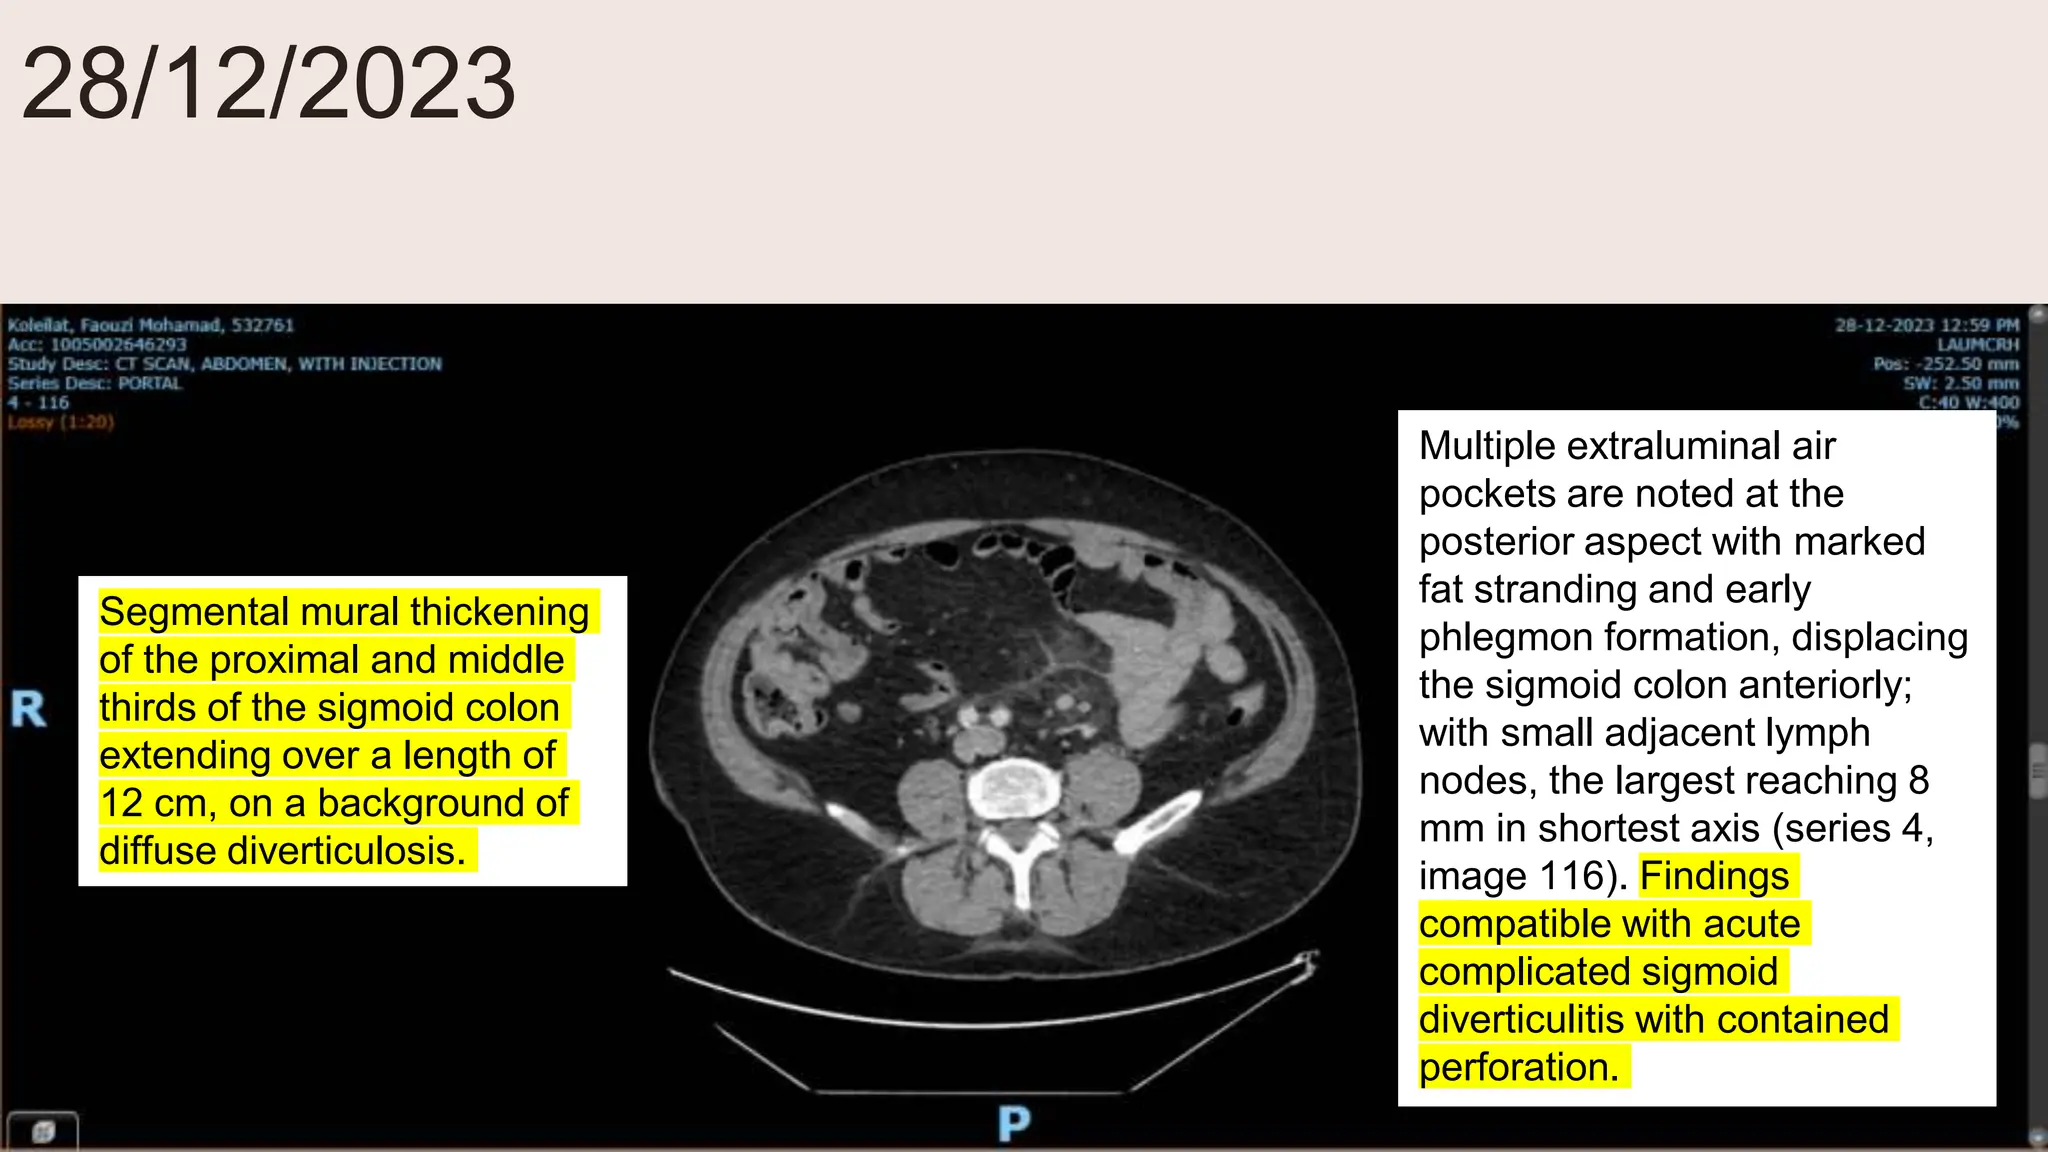

28/12/2023

Segmental mural thickening

of the proximal and middle

thirds of the sigmoid colon

extending over a length of

12 cm, on a background of

diffuse diverticulosis.

Multiple extraluminal air

pockets are noted at the

posterior aspect with marked

fat stranding and early

phlegmon formation, displacing

the sigmoid colon anteriorly;

with small adjacent lymph

nodes, the largest reaching 8

mm in shortest axis (series 4,

image 116). Findings

compatible with acute

complicated sigmoid

diverticulitis with contained

perforation.